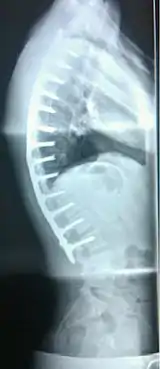

| Scheuermann's disease on lateral Xray of the T spine | |

Diagnosis is typically by medical imaging. The degree of kyphosis can be measured by Cobb's angle and sagittal balance.